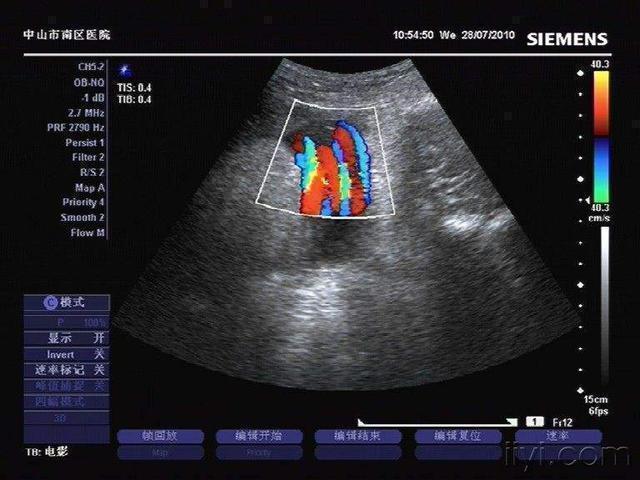

怀孕期间,胎儿总会发生许多不可控的状况。如果孕妈们发现得及时,那么宝宝就会得到有效的救助。但如果孕妈没有察觉到,宝宝可能就危险了。那么,孕妈们平时应该怎么注意这种情况呢?1. 参加医院举办的孕期培训课。基本上每个医院的妇产科,都会有这种小课堂。教孕妈们平时合理运动,以促进胎儿和妈妈身体健康,和如何均衡饮食,以及一些怀孕期间日常生活中的小常识。别看这些东西看起来不怎么起眼,但实际上在潜移默化中,会影响到孕妈们的思维。而且,这些知识总会在某些事件中起到作用。所以不仅孕妈可以去听,准爸爸们也要多陪着妻子去听听,在关键时刻做决断帮到妻子。